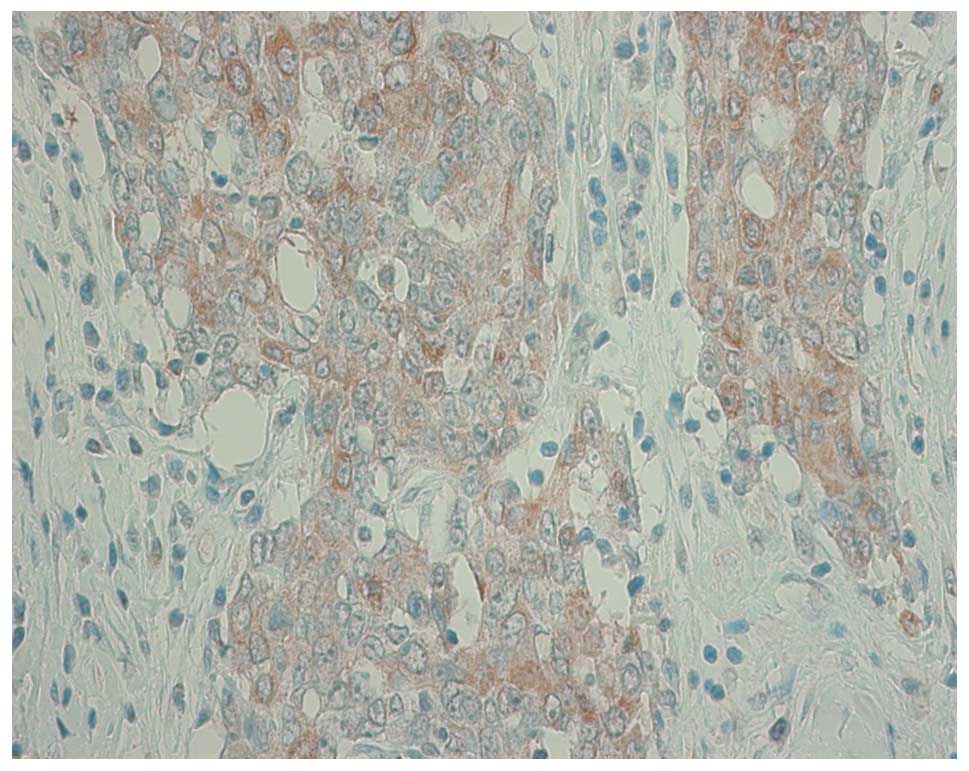

Expression of thymidylate synthase and orotate phosphoribosyltransferase in thymic carcinoma

Thymic carcinoma is a rare thymic epithelial tumor in which chemotherapy for advanced disease has not yet been established. Thymidylate synthase (TS) and orotate phosphoribosyltransferase (OPRT) protein expression levels in thymic carcinoma were evaluated as possible indicators of the anticancer activity of 5-fluorouracil (5-FU) drugs using immunohistochemistry (IHC). A total of 24 samples of thymic carcinoma were used in the present study. The tumor sections were immunohistochemically stained for TS and OPRT. As a comparison with thymic carcinoma, we also assessed the TS and OPRT protein expression levels in 55 lung cancer samples. The TS expression was positive in 12 of 24 thymic carcinoma samples (50%) and OPRT expression was positive in 10 (42%). The association between TS and OPRT expression and Masaoka stages of thymic carcinoma was analyzed. The TS and OPRT expressions in stage IV were significantly higher compared to that in stages I, II or III. We also compared the TS and OPRT expression levels between thymic carcinoma and lung cancer (33 adenocarcinomas and 22 squamous cell carcinomas). TS expression in thymic carcinoma was significantly lower compared with lung squamous cell carcinoma. OPRT expression in thymic carcinoma was significantly higher compared to lung adenocarcinoma. The combination of a relatively low expression of TS and high expression of OPRT suggests an improved antitumor effect of 5-FU drugs in thymic carcinoma compared to in lung carcinoma.

Figure 1

Figure 2

Figure 3

Figure 4

Figure 5